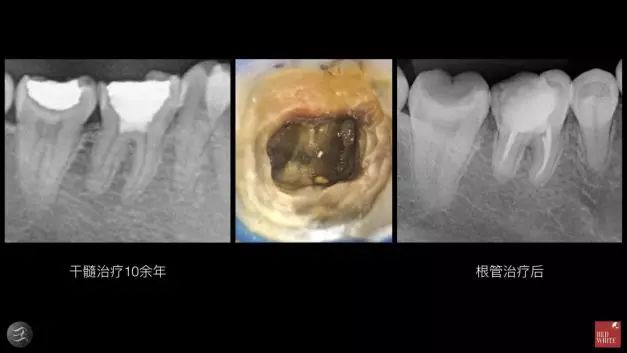

▲如上图两个转诊过来的病例都已经治疗10余年,患者没有任何症状,第二个根管治疗后反而出现了自发性地隐痛。